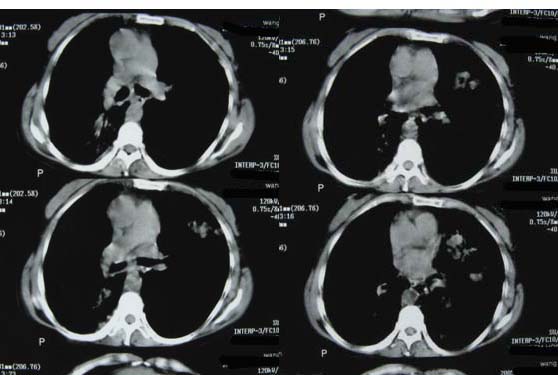

1.考虑双肺转移,建议增强ct及纤支镜;

2.双肺肺气肿,支扩伴少许感染;

3.双中上肺陈旧性病灶。

1、双肺多发转移瘤可能性大,建议进一步检查。

2、支气管扩张

右上肺后段及左上肺舌段片状影,考虑双肺结核。

双肺弥漫性结节影,考虑双肺转移性肿瘤。